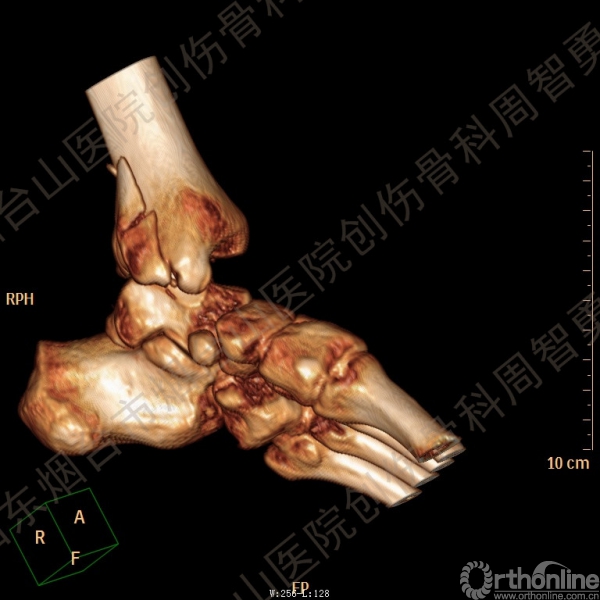

患者一般情况可,左踝关节肿胀,见皮下瘀斑,内、外、后侧有压痛,左踝关节主动运动受限,左足皮肤感觉、血供未见明显异常,左足趾各关节可主动运动。左踝关节正位X线片和CT重建示内踝内上方双层骨皮质影(图1a,c),CT示后侧骨折块分为后内侧骨折块和后外侧骨折块(图2a,b),后内侧骨折块累及内踝后丘,后丘骨折线呈冠状位(图2c),后内侧骨折块腹侧有向近端塌陷的小块骨软骨骨折块(图2d),CT也显示Chaput骨折块(图1c,2e)。

经典的后踝骨折发生于低能量旋转外力所致的踝关节骨折;标准pilon骨折见于高能量轴向暴力;而后侧pilon骨折是旋转外力和轴向暴力共同作用的结果,属于中等能量的损伤。踝关节骨折中的后踝骨折源自下胫腓后韧带的牵拉,骨折块位于后外侧,常为单一的三角形骨折块,大小从关节外片状骨折到累及胫骨远端关节面矢状径的40%(图4a)。后侧pilon骨折中的后侧骨折块较大,累及内踝后丘(三角韧带深层起点)在内的整个胫骨远端后侧,分为后内侧骨折块和后外侧骨折块,后内侧骨折块腹侧有向近端塌陷的骨软骨骨折块(图4b)。后侧pilon骨折中的内踝骨折线并不是水平位而是冠状位,可合并内踝前丘骨折。后侧pilon骨折踝关节正位X线片示特异性的内踝内上方双层骨皮质影(图1a,c)。这是由于后内侧骨折块的骨折线延伸到胫骨远端骨骺和干骺端的内侧骨皮质,其移位后的边缘成像所致。水平位CT显示后侧骨折块分为后内侧骨折块和后外侧骨折块,矢状位CT示后内侧骨折块腹侧有向近端塌陷的骨软骨骨折块。

②创伤解剖:后踝骨折块较大,累及内踝后丘在内的整个胫骨远端后侧,分为后内侧骨折块和后外侧骨折块,后内侧骨折块腹侧有向近端塌陷的骨软骨骨折块;可合并内踝前丘骨折、下胫腓前结节骨折或下胫腓联合分离

↑ 图 2a

↑ 图 2b

↑ 图 2c

↑ 图 2d

↑ 图 2e

图 2 术前CT,显示后侧骨折块分为后内侧骨折块和后外侧骨折块(a,b),后内侧骨折块累及内踝后丘,后丘骨折线呈冠状位(c),箭头所示后内侧骨折块腹侧有向近端塌陷的小块骨软骨骨折块(d),Chaput骨折块(e)